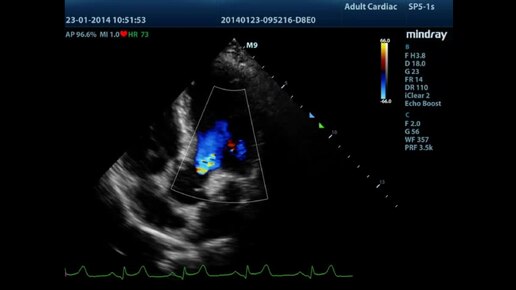

Кинопетля Mindray M9 - 5CH Color

Кинопетли УЗИ-сканера Mindray M9

Далее: Кинопетля Mindray M9 - Kidney Color